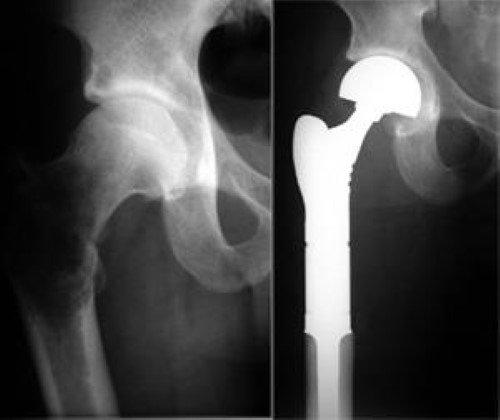

special hip replacement for metastatic bone disease

A 57-year-old man with metastatic kidney cancer and progressive right hip pain requiring a special form of total hip replacement.

Reproduced with permission from Weber K, Lewis V, Randall RL, Lee AK, Spingfield D: An approach to the management of the patient with metastatic bone disease, in Helfet DL, Greene WB (eds): Instructional Course Lectures, Volume 53. Rosemont, IL, American Academy of Orthopaedic Surgeons, 2004.

Hip or femoral head and neck lesions, whether impending or actual, rarely heal. The procedure of choice to treat this type of metastasis is, therefore, joint replacement. The decision about whether to perform a partial (hemiarthroplasty) or total hip reconstruction depends on the involvement of the acetabulum (hip cup).

hip replacement for metastatic bone disease

(Left) An X-ray of a pathological fracture of the hip. There is extensive destruction of the bone around the hip. (Right) An X-ray of the same leg after the upper femur was replaced by an artificial implant.

Reproduced from Schwartz HS, ed: Orthopaedic Knowledge Update: Musculoskeletal Tumors 2. Rosemont, IL, American Academy of Orthopaedic Surgeons, 2007, p 389.